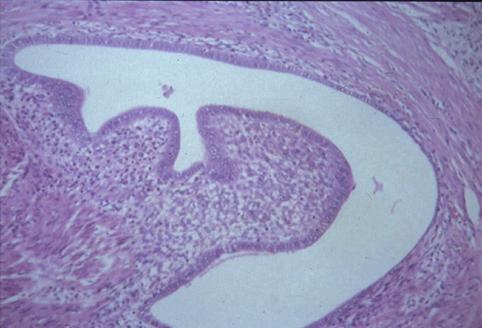

Endometriosis causado por canal intestinal, que fue operado por motivo constricción de Colon Signoides.

Lesión que asemeja tumoración/Mucosa aberrante

colon/sigmoides

Micro